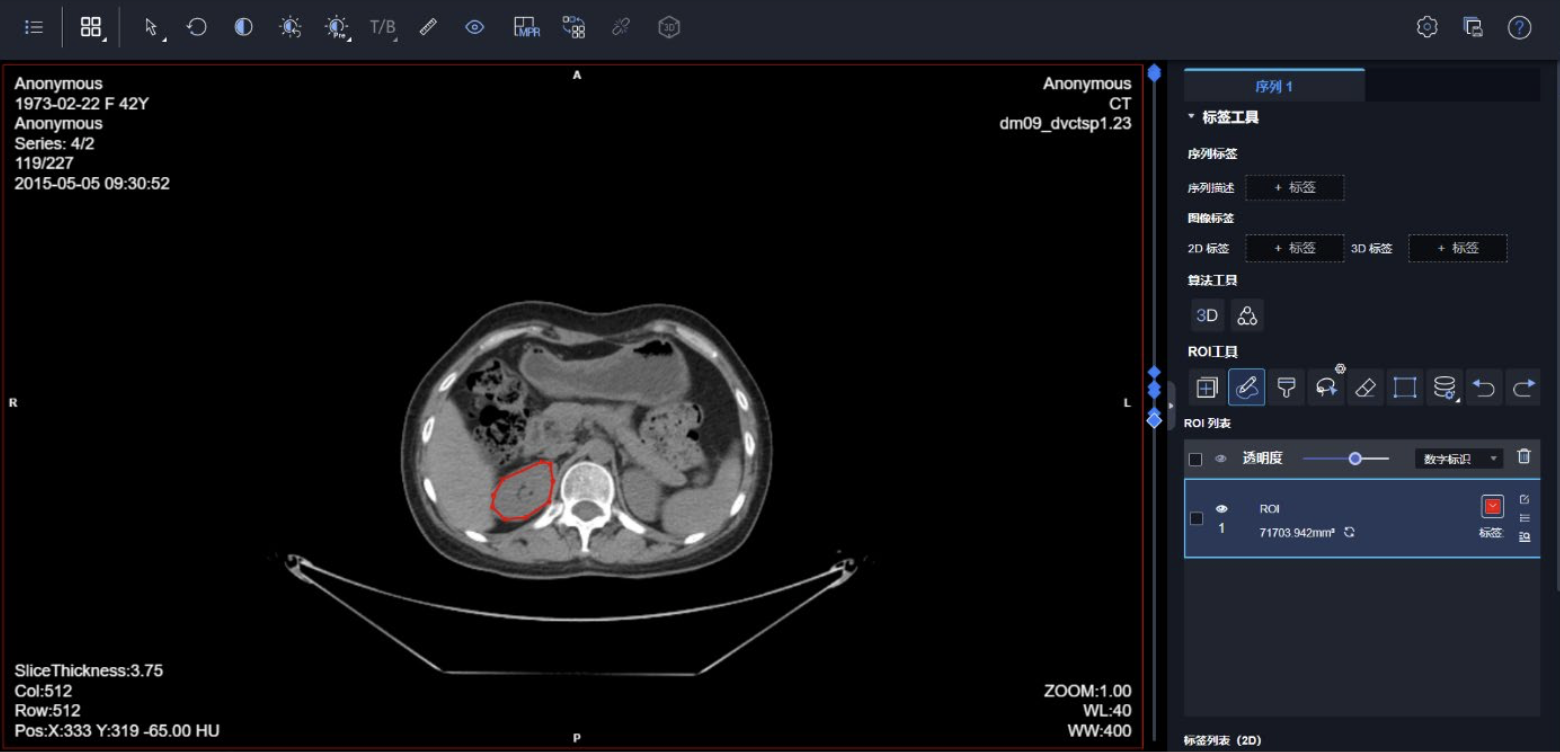

数据标注:提供手动标注(可以调用本机的3d slicer),也可以在平台上标注,平台的标注功能带了AI模型,比如腹部器官他可以自动识别,如果你要标注这些器官那很简单。你也可以在平台上训练了一个模型后,调用自己的模型进行标注

影像组学模块:在组学模块中包含三个子模块:特征提取、特征选择以及机器学习模型的训练。特征提取是在ROI区域提取图像相关的统计特征;特征选择是在特征提取的基础上做相关性分析;机 器学习模型的训练是在特征提取以及特征选择的基础上做相关分类、回归。